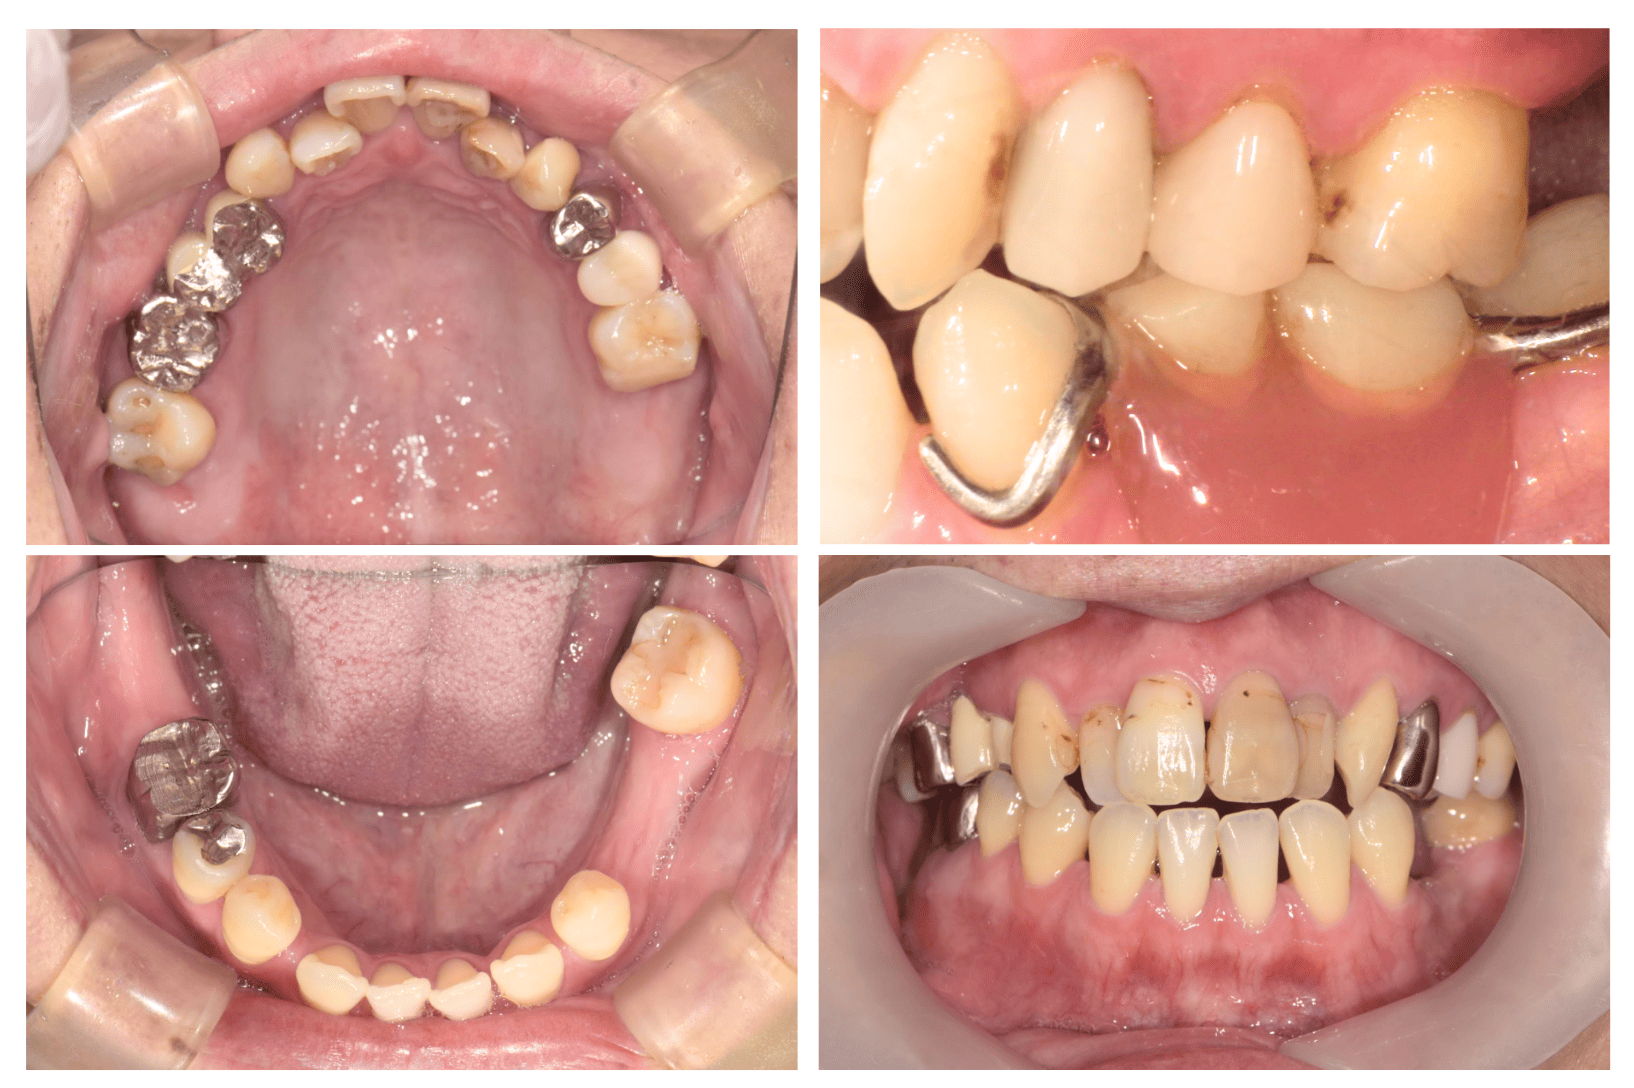

治療経過(咬合診断の結果を患者さんの口腔内に落とし込みかみ合わせの補正を行いながら虫歯治療や入れ歯治療を行った)

歯周病治療も行い現在は安定し定期的メンテナンスの移行中

通院目的 前歯で物が噛めないがどこの歯医者でも治せないと言われた

診断 下顎劣成長による開咬 小下顎症(骨格性2級1類)

処置内容 (または主訴) 根本治療はSSROを伴う矯正治療だが 咬合診断を下にする咬合高径の低下